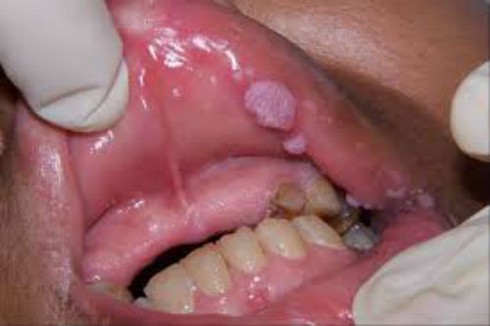

Hình ảnh sùi mào gà ở khoang miệng. |

Sau khi đi khám tại một bệnh viện, bác sĩ cho biết chị bị sùi mào gà ở khoang miệng. Chị K. về nhà điều trị đã khỏi được một thời gian. Tuy nhiên, gần đây chị thấy con gái nhỏ 2 tuổi cũng có các biểu hiện xuất hiện ổ sùi quanh miệng và phần lưng. Chị K. hoang mang vô cùng vì em bé còn quá nhỏ. Chị đã đưa con đi kiểm tra kết quả dương tính với HPV – vi rút gây ra sùi mào gà ở người.

Ngay sau đó, chị K. đã đưa bé đi khám da liễu và điều trị nhưng bệnh chậm tiến triển. Khi đến phòng khám, bác sĩ cho biết quanh môi và miệng của chị K. vẫn còn xuất hiện ổ sùi li ti. Nguyên nhân khiến con chị bị sùi mào gà có thể do người mẹ hôn con mà không để ý.